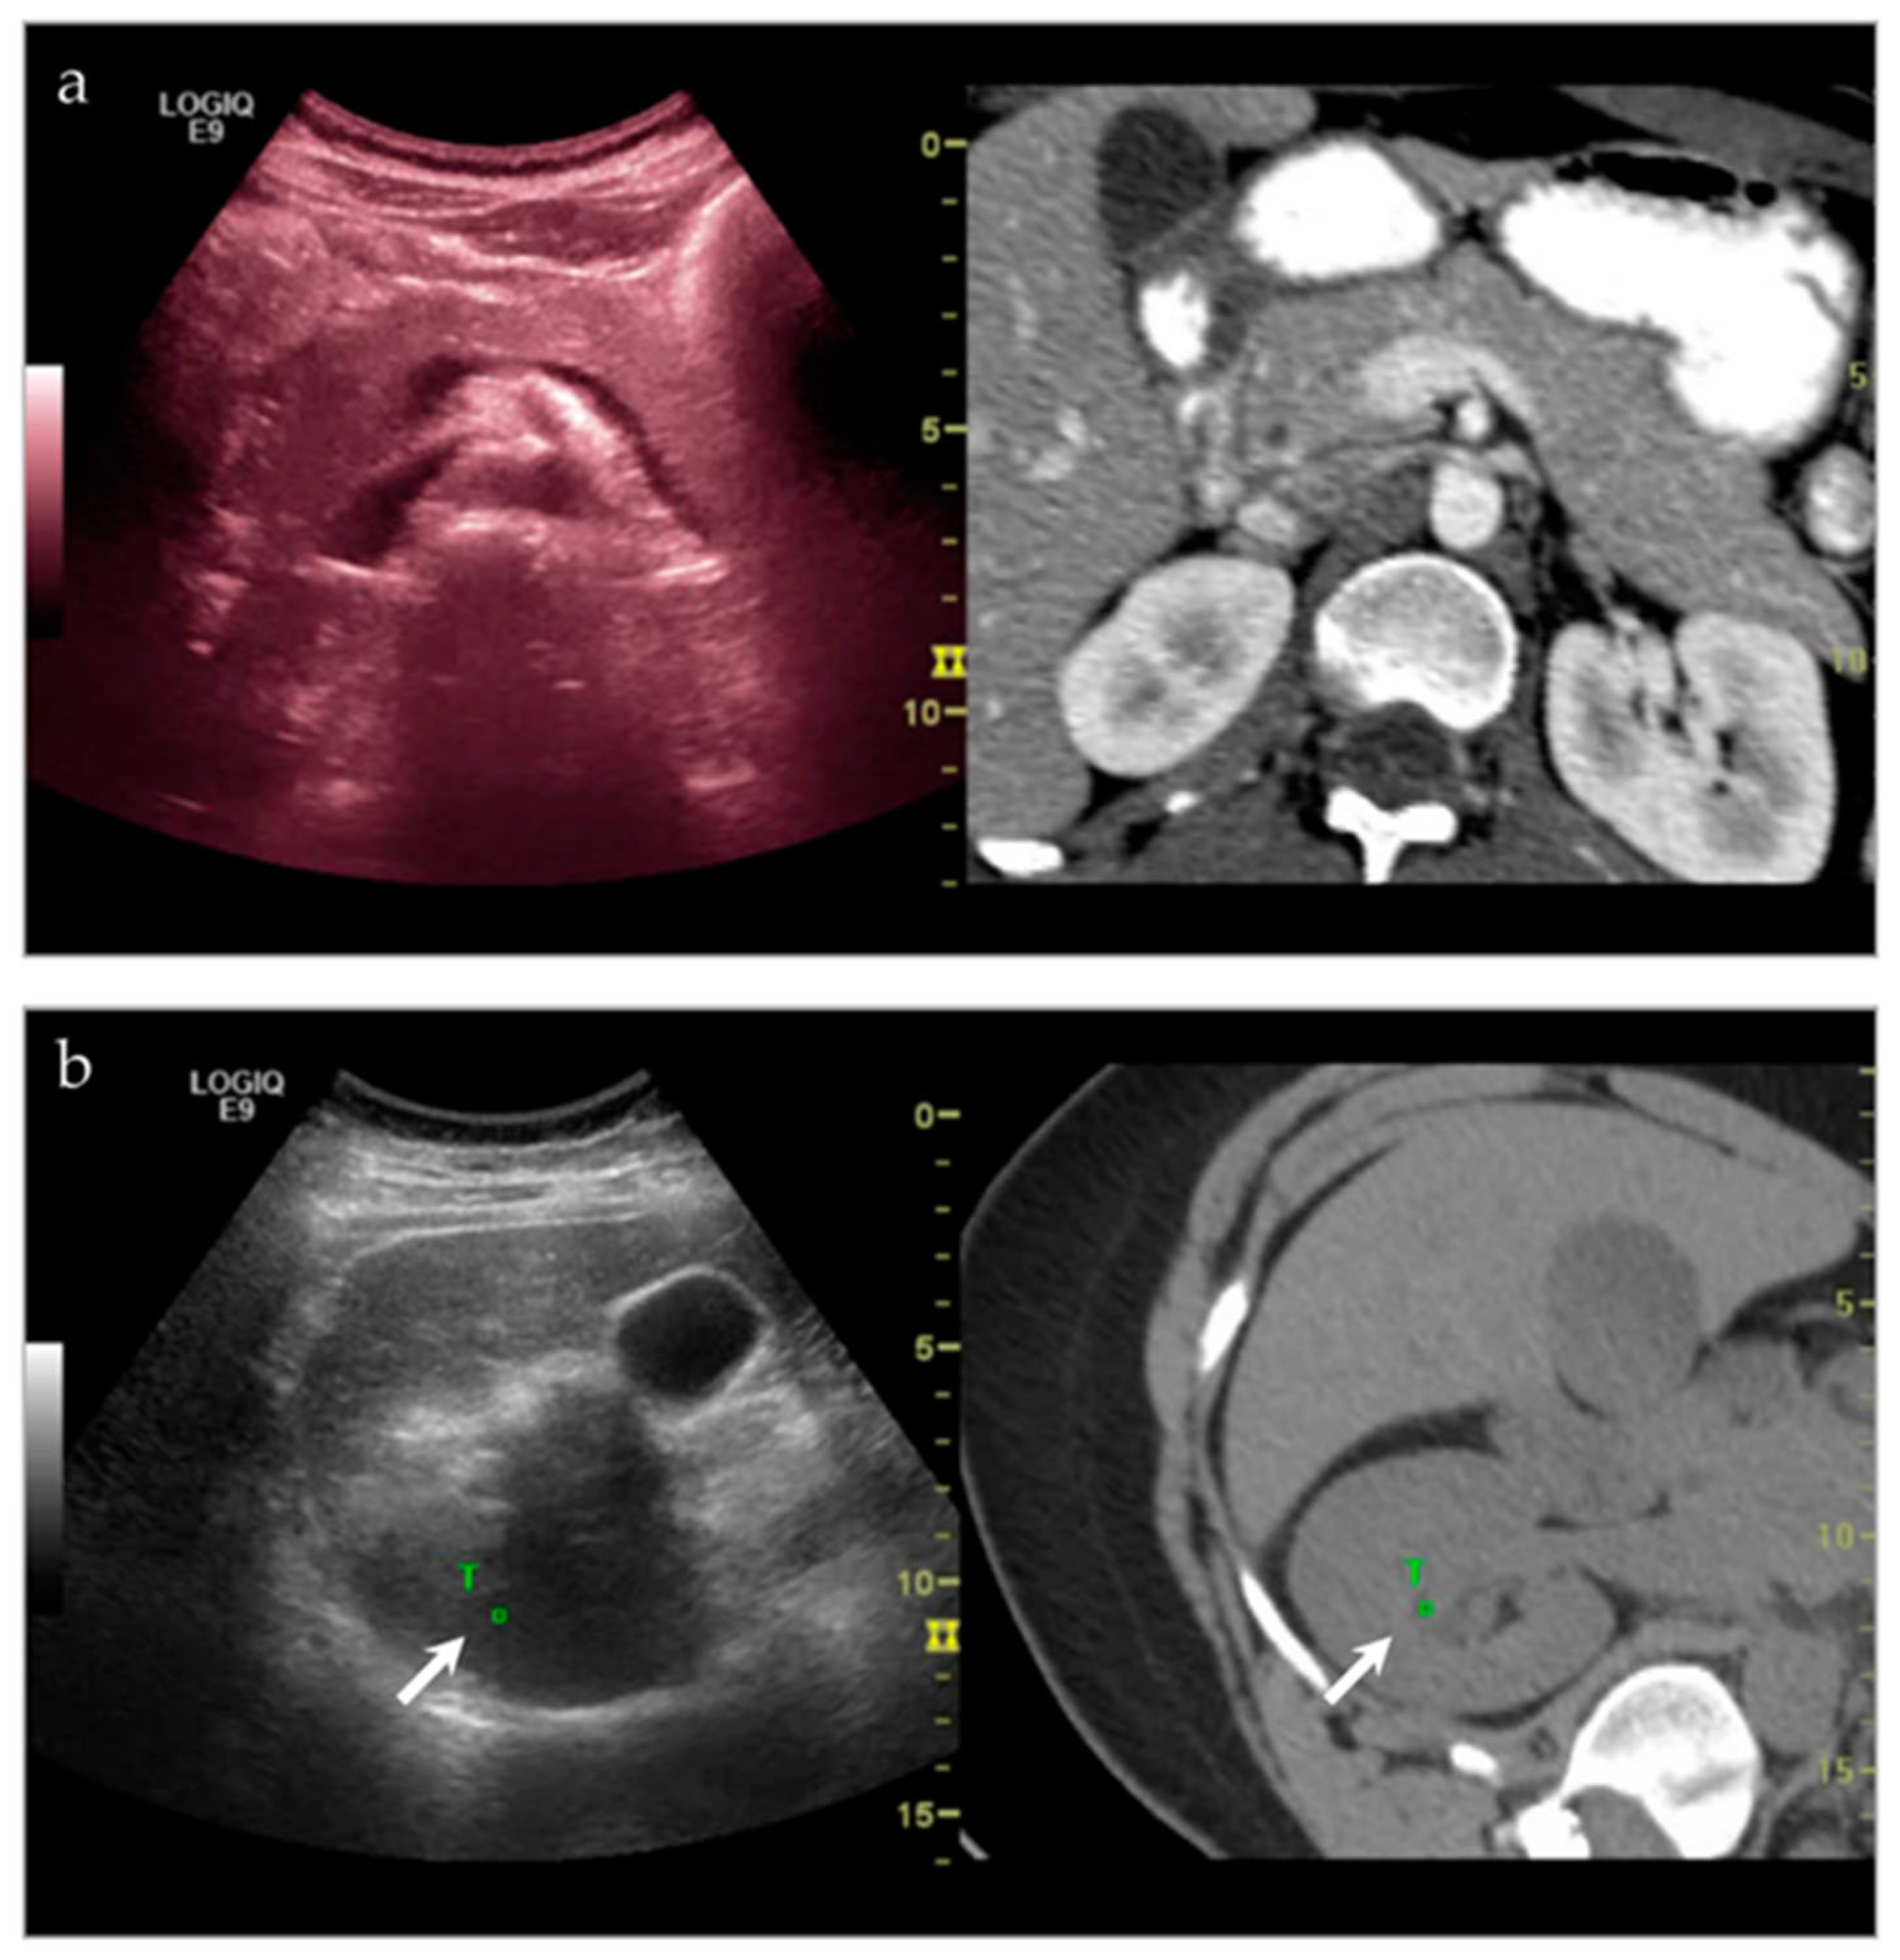

| NA **/F | Right psoas muscle | US-CT fusion | Abscess | Infection |